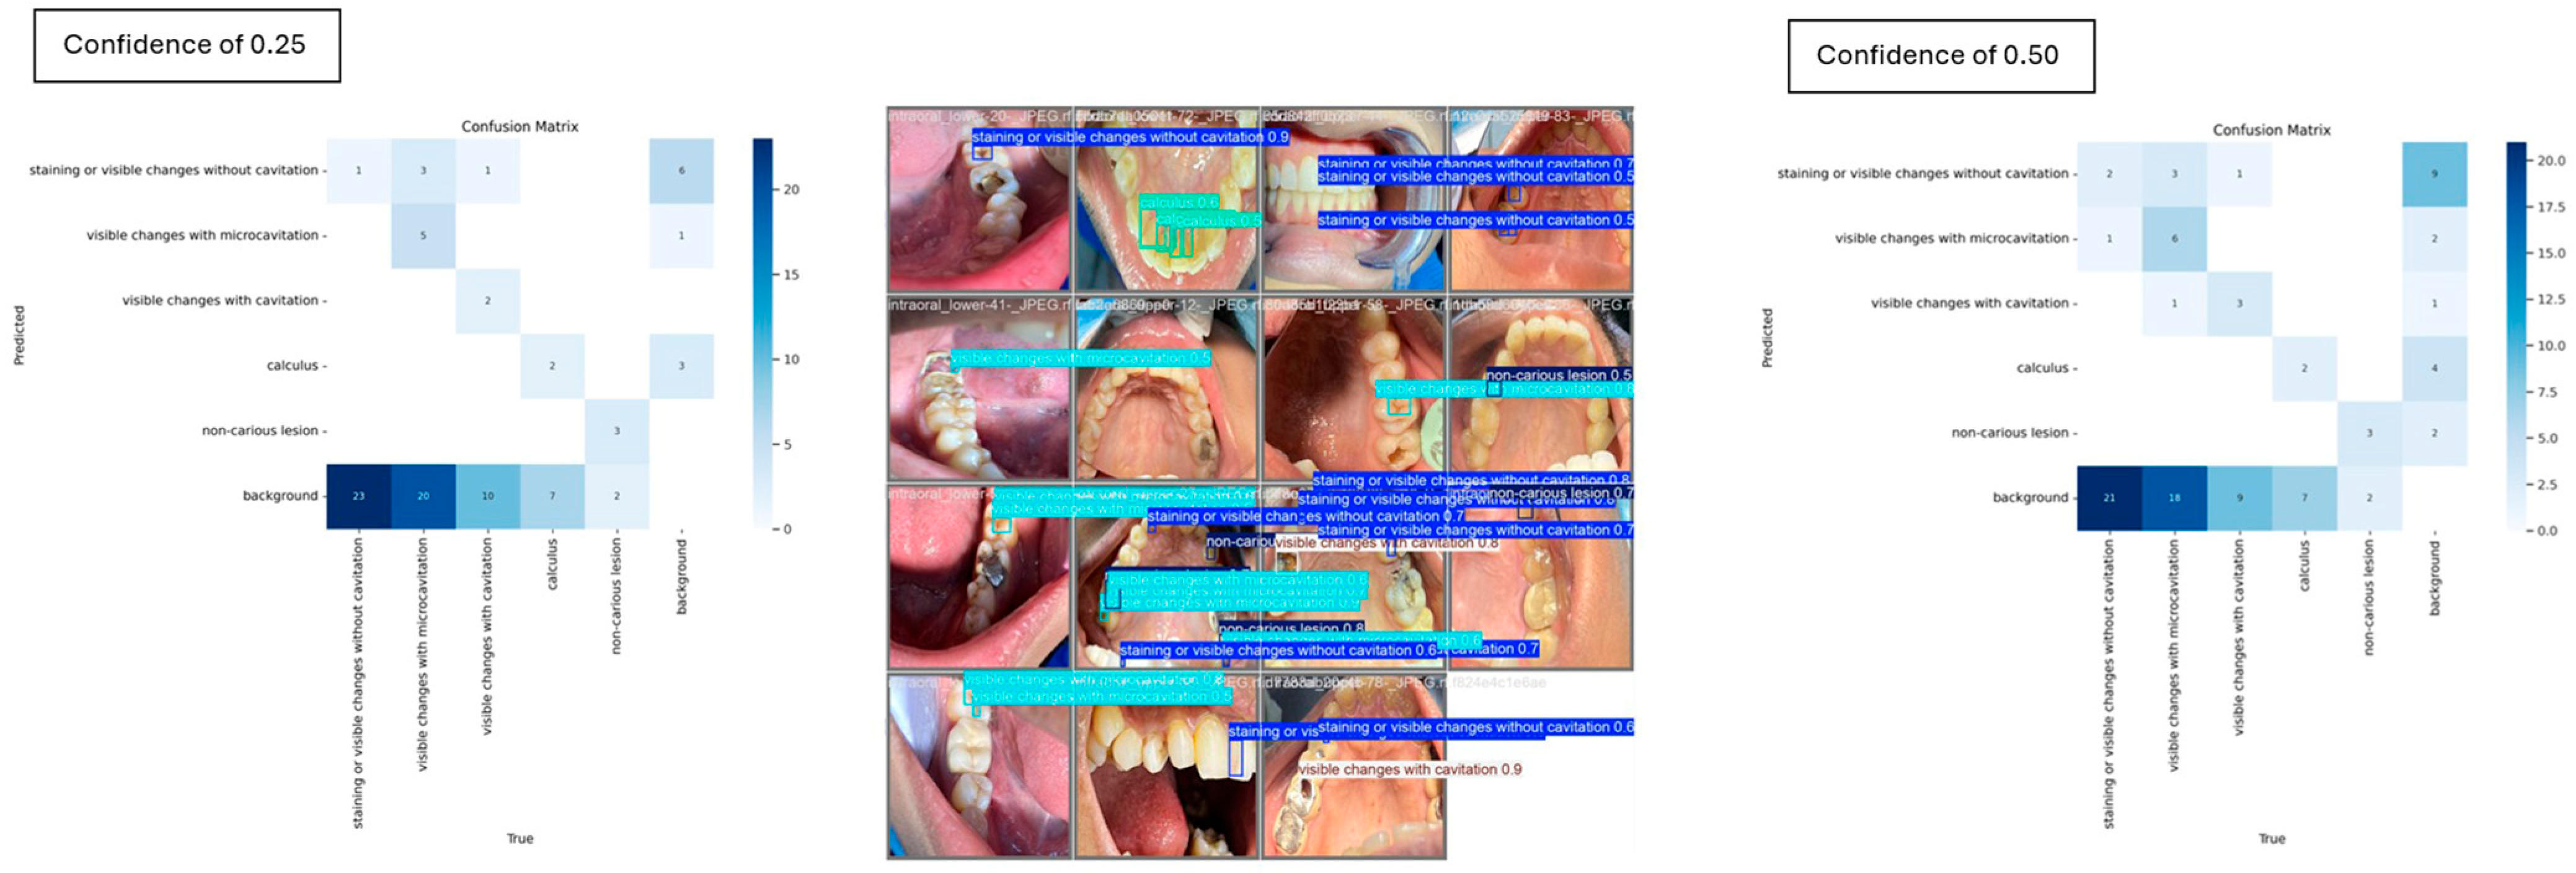

The confidence threshold defines the minimum score (ranging from 0 to 1) required for a model to consider a predicted object valid [20,21]. Adjusting this threshold allows for evaluation of detection reliability: higher thresholds reduce false positives by filtering uncertain detections, while lower thresholds may increase the number of false positives [20]. To examine performance under different detection certainty levels, the model was evaluated using two confidence thresholds, 0.50 and 0.25.

YOLOv8 achieved a mAP@50 of 37%, at a confidence threshold of 0.25, which decreased to 35% when the threshold was raised to 0.5. Likewise, the mAP@50-95 values dropped from 18% at 0.25 to 17.7% at 0.5. These metrics indicate that a lower threshold allowed YOLOv8 to identify more instances, albeit with greater risk of false positives.

Precision and recall metrics also showed significant differences across thresholds:

• At a threshold of 0.25 (Table 1), the model achieved a precision of 42.3% and a recall of 31.3%.

• At a threshold of 0.5 (Table 2), precision increased to 54.7%, while recall dropped to 15.6%.

For the carious and non-carious lesion classes, YOLOv8 demonstrated strong performance in detecting visible changes associated with cavitation, consistently achieving 100% precision. However, at a confidence threshold of 0.5, the model completely failed to detect instances of the calculus class, yielding 0% mAP, precision and recall. When the threshold was reduced to 0.25, detection performance improved modestly, with the calculus class achieving an mAP of 16.7%. The pairwise confusion matrix distribution across the two thresholds is illustrated in Figure 6, highlighting the impact of threshold adjustment on class-specific detection outcomes.

Figure 6. Individual misclassification distribution across the two confidence thresholds.